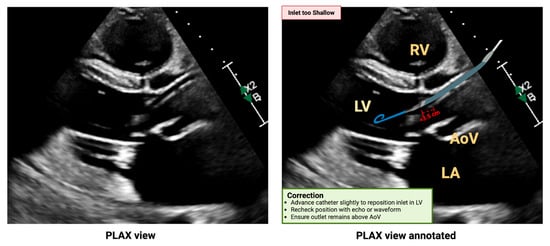

5.2. Malposition

5.2.2. Shallow Malposition

- Tran, T.; Mudigonda, P.; Mahr, C.; Kirkpatrick, J. Echocardiographic imaging of temporary percutaneous mechanical circulatory support devices. J. Echocardiogr. 2022, 20, 77–86. [Google Scholar] [CrossRef]

- Sacks, S.; Feinman, J. A 2024 Update From the American Society of Echocardiography: Multimodality Imaging for Patients With Left Ventricular Assist Devices and Temporary Mechanical Circulatory Support. J. Cardiothorac. Vasc. Anesth. 2025, 39, 1919–1923. [Google Scholar] [CrossRef]

- Burzotta, F.; Trani, C.; Doshi, S.N.; Townend, J.; van Geuns, R.J.; Hunziker, P.; Schieffer, B.; Karatolios, K.; Moller, J.E.; Ribichini, F.L.; et al. Impella ventricular support in clinical practice: Collaborative viewpoint from a European expert user group. Int. J. Cardiol. 2015, 201, 684–691. [Google Scholar] [CrossRef]

- Baldetti, L.; Beneduce, A.; Chieffo, A.; Scandroglio, A.M. Technical tips for inserting and positioning the Impella device. Card. Interv. Today 2023, 17, 60–65. [Google Scholar]